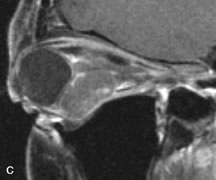

On MRI, uveal melanomas have a typical appearance that helps to differentiate them from other primary and secondary intraocular tumors as well as choroidal detachments. Pigmented melanomas are hyperintense on Tl-weighted images, hypointense on T2-weighted studies, and hyperintense on proton density–weighted examinations (Fig. 24).30,31,50,80–82 These signal characteristics have been attributed to the paramagnetic properties of melanin because of stable free radicals that shorten the T1 and T2 relaxation times. Moderate enhancement is seen on postgadolinium T2-weighted images. Gadolinium-enhanced T1-weighted images are particularly sensitive in detecting choroidal melanomas.83 MRI may be less sensitive in detecting extrascleral extension of tumor than echography performed by an experienced ultrasonographer.84

Fig. 24. A. T1- and (B) T2-weighted MR scans demonstrate a small nodular intraocular mass (arrows) that is very hyperintense on the T1-weighted scan and hypointense on the T2-weighted image. This signal intensity pattern is due to the presence of free radicals within melanin granules. C and D. Postcontrast fat-suppressed T1-weighted scans demonstrate homogeneous intense enhancement of the lesion and no evidence of seleral penetration or optic nerve invasion.

Tumors metastatic to the choroid are hyperintense on T1- and T2-weighted images.24 The signal characteristics, however, may be similar to those seen with choroidal melanoma. Choroidal hemangiomas, on the other hand, have an intermediate signal on T1-weighted sequences and become hyperintense on T2-weighted images50 as well as proton density–weighted images.81